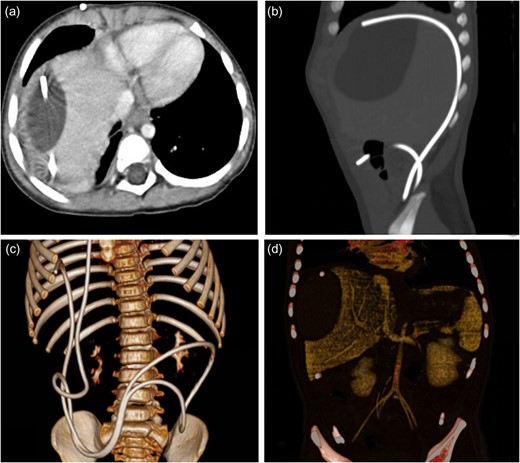

A female child, at the age of 2 years, was admitted to our hospital because she was not able to walk alone. This child patient had undergone ventriculo–peritoneal (VP) shunt procedure for hydrocephalus confirmed by magnetic resonance imaging (MRI). On the 50th day after the surgery, she mainly complained of intermittent fever and mild abdominal pain for 12 days. Physical examination showed no obvious abnormality. Blood routine examination showed white blood cell count was 8.31 × 109/l, with neutrophils 60.7%, lymphocytes 30.8%. C-reactive protein was 81 mg/l. Abdominal ultrasonography indicated ascites. Abdominal enhanced computed tomography (CT) scan showed that water-like hypointense mass in sub-capsular of liver, which was homogeneous and well-defined, the max cross-sectional area was ~6.04 × 3.85 cm, multiple catheter images were seen in abdominal cavity, also showed that there was no enhanced images in the mass (Fig. 1). Accordingly, it was necessary to perform exploratory operation. Operation found that a little of clear fluid was accumulated in abdominal cavity and the distal end of catheter was located at the sub-capsular of diaphragmatic surface of right liver. The distal end was pulled out slowly and sub-capsular effusion overflowed. The VP shunt catheter was neither disconnected nor fractured, and was replaced subsequently in abdominal cavity. Postoperative CT scan showed that a small part of effusion remained in the liver contour and the distal catheter in the left abdominal cavity (Fig. 2). The child was discharged uneventfully in 1 week postoperative.

The enhanced CT before operation. (a) Axial CT showed water-like hypointense mass and catheter image in the liver contour. (b) Sagittal CT revealed catheter image under liver capsule and the homogeneous and well-defined mass in the liver contour. (c) Three-dimensional image of catheter in abdominal cavity. (d) The mass in the liver contour.